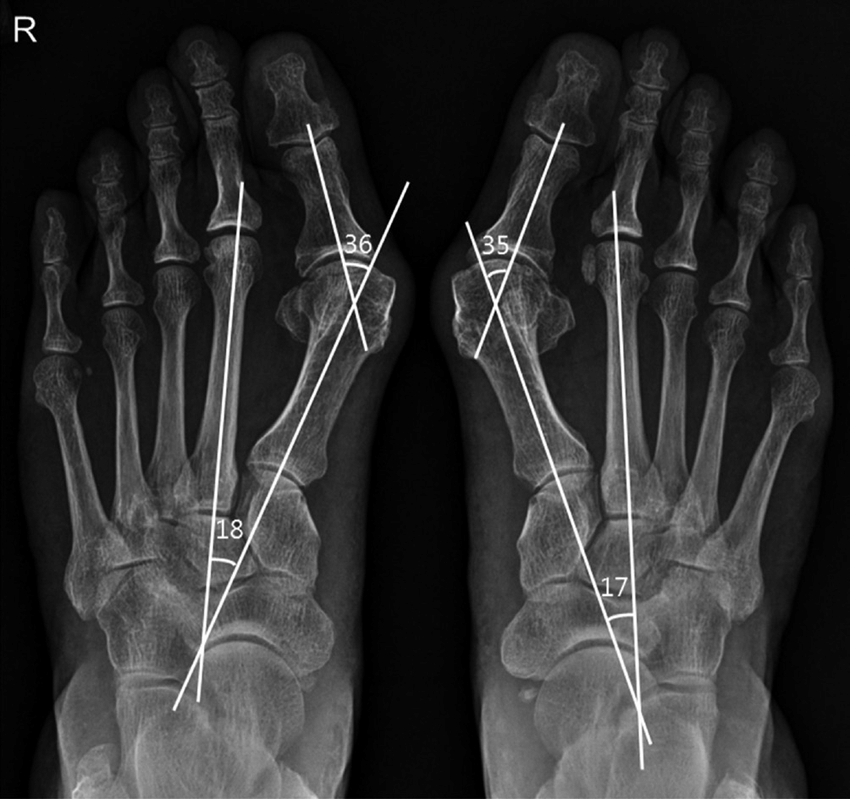

일단 치료 방식을 결정하기 전에, 엑스레이로 '무지외반증' 정도를 평가합니다.

기본 엑스레이를 통해 각도를 측정하는데 동일한 AP view 에서 주로 평가합니다.

1. HVA : Hallux Valgus Angle < 15도 이하 정상

2. IMA : Inter Metatarsal Ange < 9도 이하 정상

3. DMAA : Distal Metatarsal Articular Angle < 10도 이하 정상

선을 그을때 대부분 중족골의 중심인 선과 근위 족지의 각을 이용하도록 합니다. 원위 중족골 관절각도(DMAA)는 중족골 선의 90도인 선과 근위 족지의 관절에서 이은 선의 두 각도를 의미합니다. DMAA 가 증가되어 있으면 연부조직의 재건을 하는 것이 좋습니다. (DMAA 가 20도 이상인 경우에는 distal + Akin, distal biplane chevron, Double (distal + porx) 등 복합교정을 이용해야하고, 단순한 교정으로는 교정이 어렵습니다. )

위의 정상 수치보다 크게 되면 무지외반증으로 진단이 가능합니다.